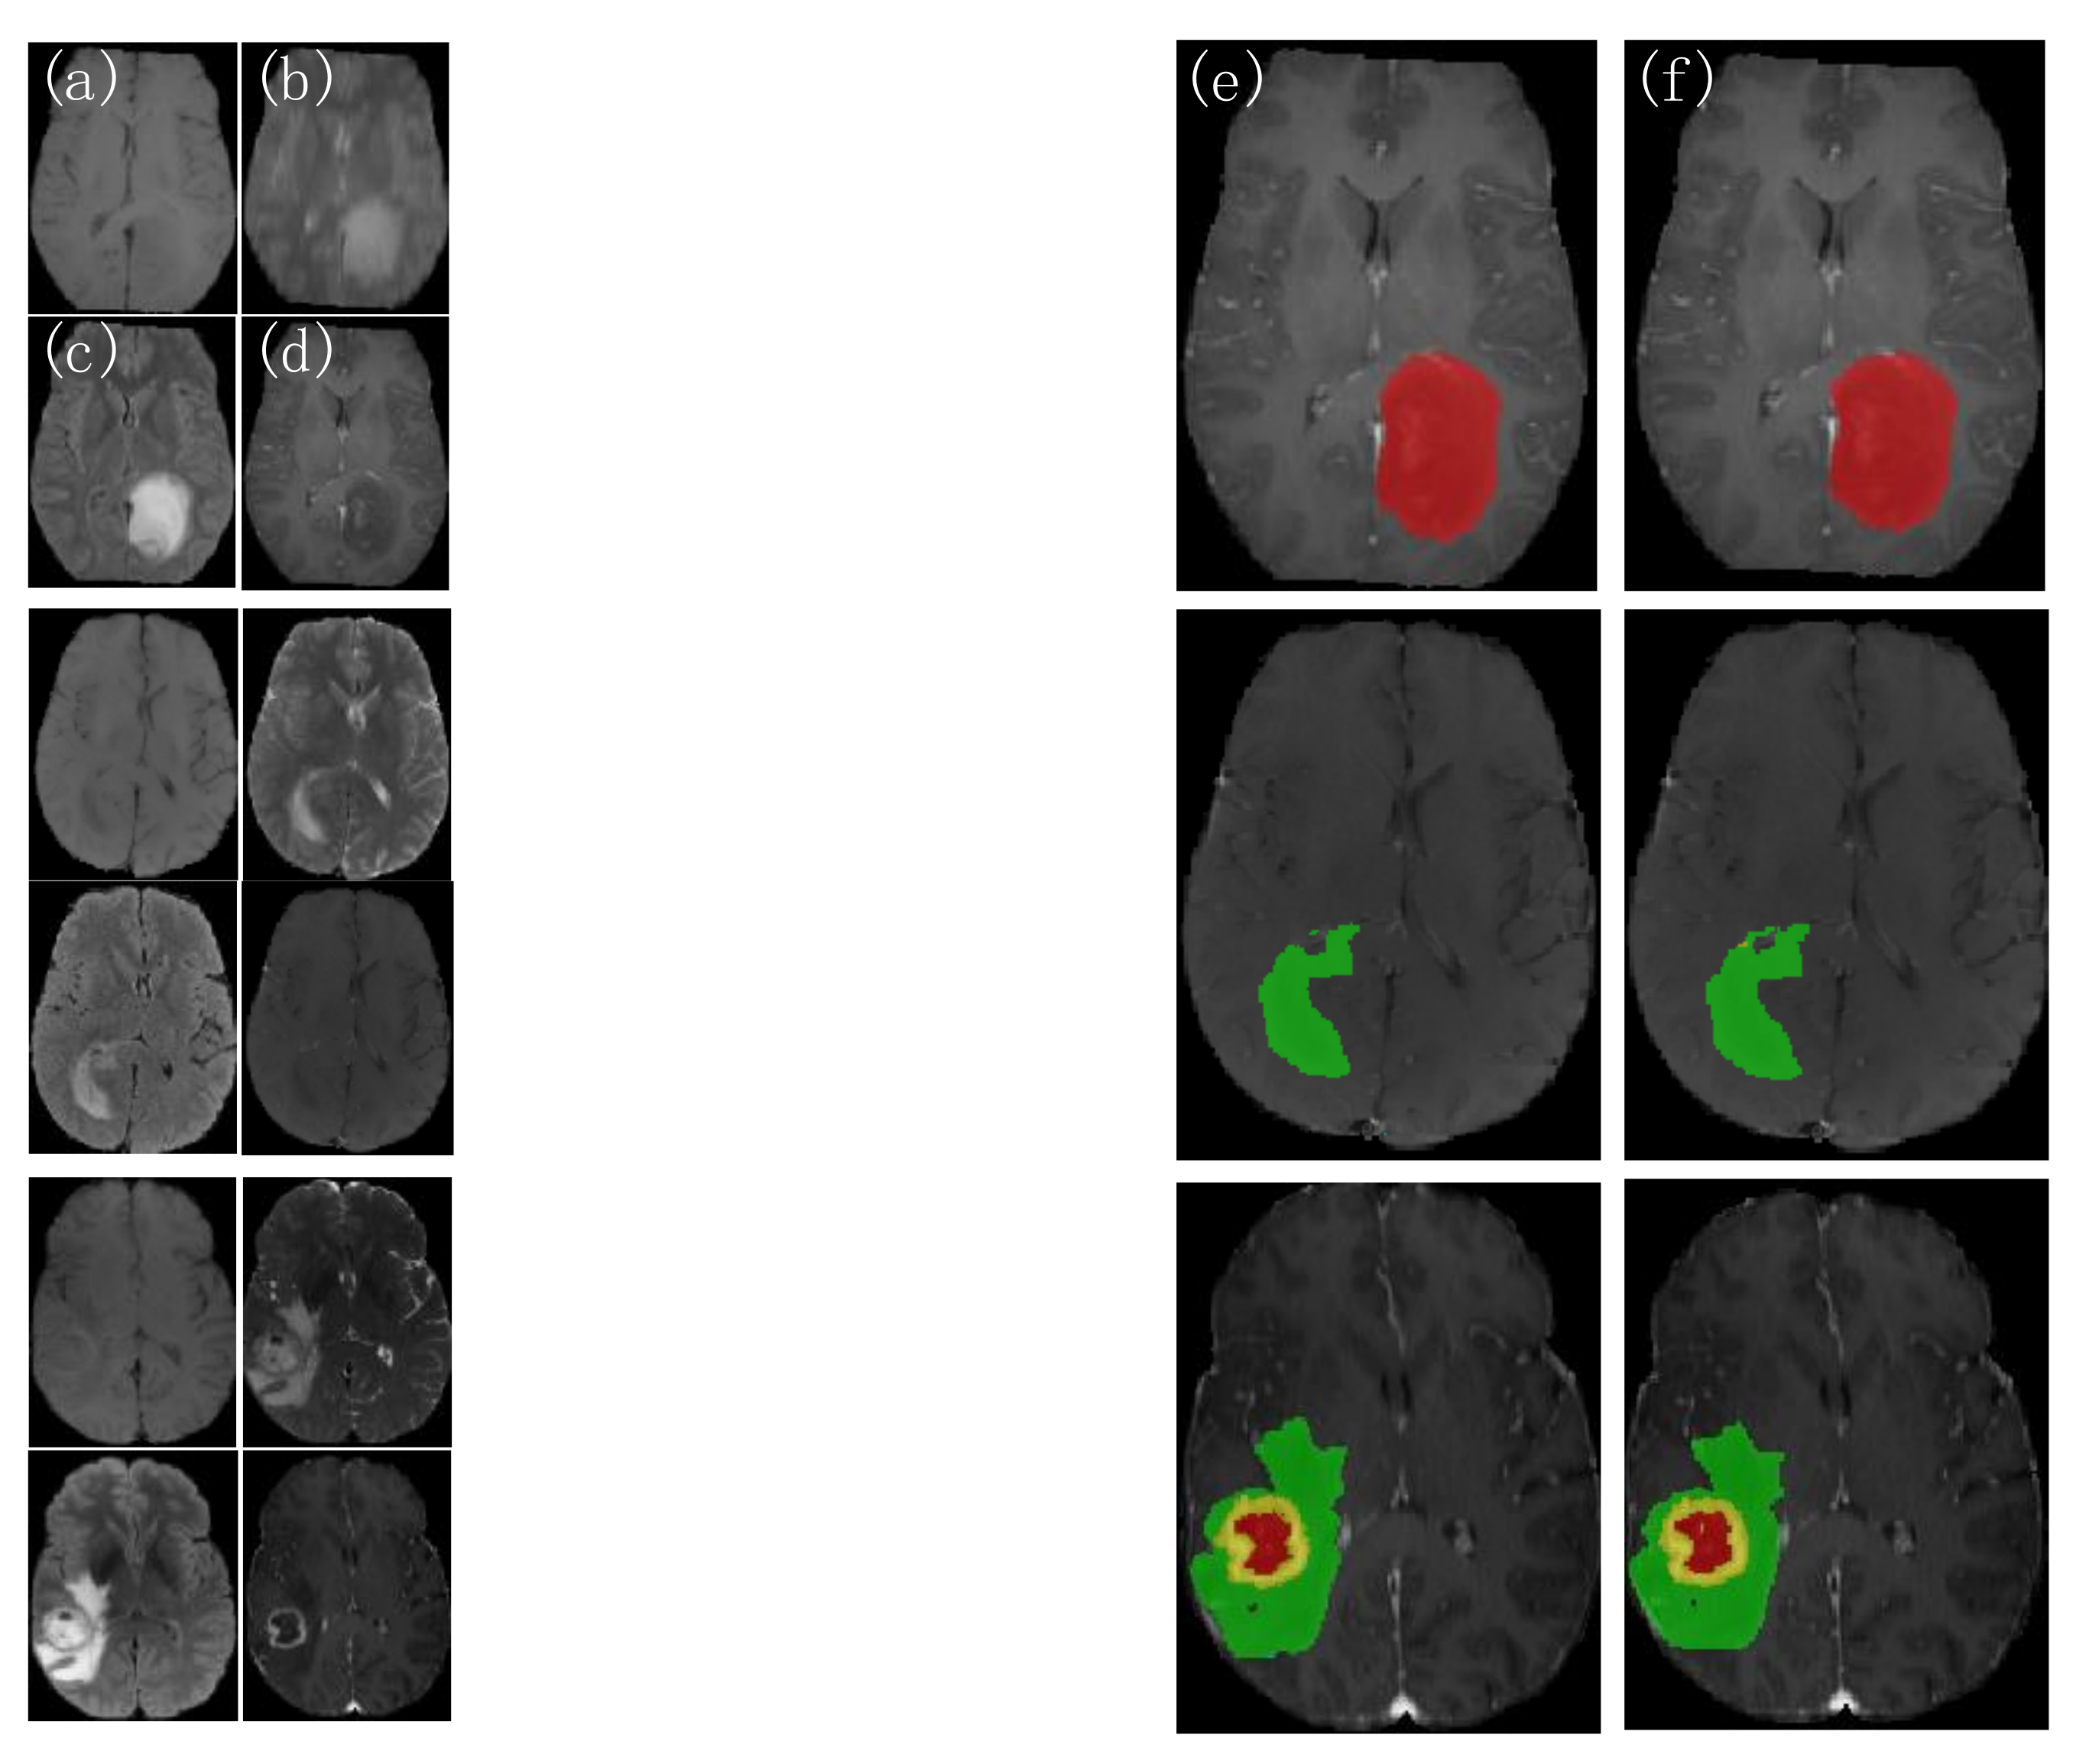

4.3.1. Analysis of the Visualization Results

3.2. Multimodal Fusion on MRI Data

3.2.1. MRI Datasets